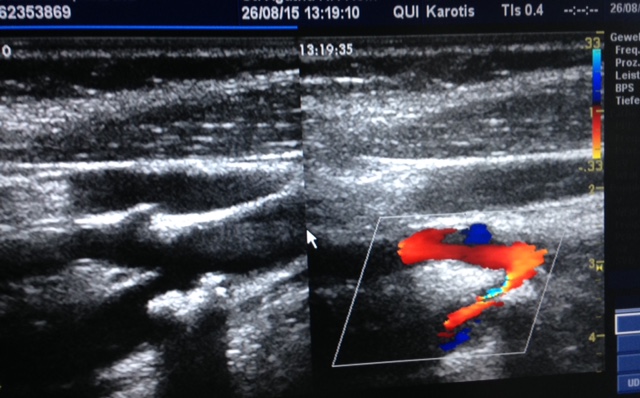

Ultraschall einer Engstelle eines Hirngefäßes

• Ultraschall des Herzens und der Hirngefäße sowie